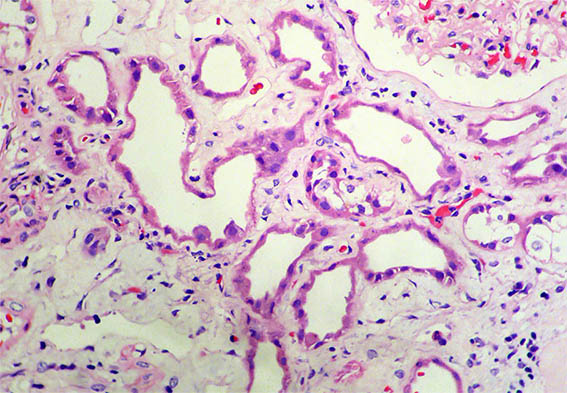

Kidney biopsy is done. Look at the pictures.

Figure 2. H&E, X200.